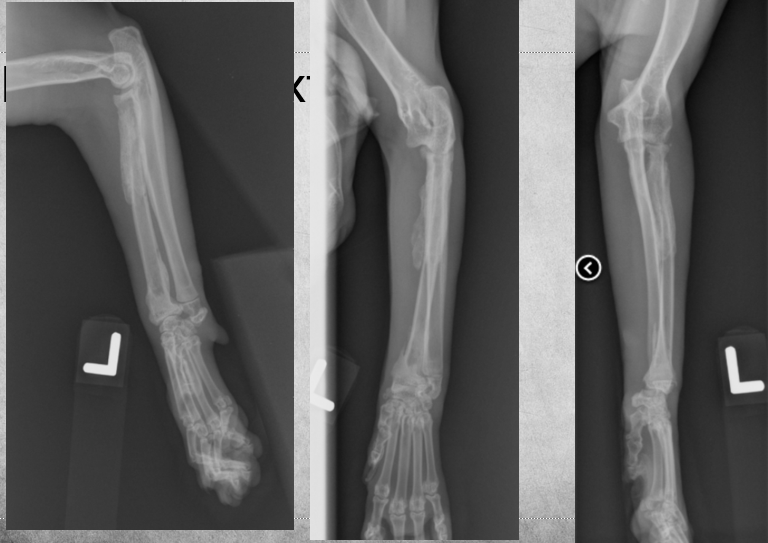

Q

4 yo toy poodle, male

Fell down from sofa 6 weeks ago

Not using left front leg

Visited other clinic

No fracture detected

Fixed bandage for 3 weeks

Still not using the leg

Human hands and other artefacts

Transverse fracture of radius and ulna

Visible milk tooth root (upper canine)